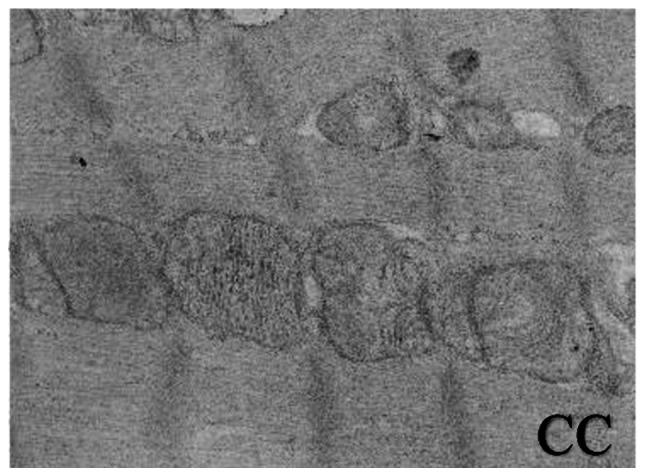

To investigate the effects of propofol on myocardial ischemia reperfusion in rats with type 2 diabetes, male adult rats were divided into five groups: Sham-operation (CC), ischemia-reperfusion (CI), low-dose propofol (LP), moderate-dose propofol (MP) and high-dose propofol (HP). The LP, MP and HP groups were administered with 6, 12 and 24 mg/kg/h propofol, respectively, prior to occlusion. Heart rate (HR), left ventricular systolic pressure (LVSP) and the rate (dp/dt max) of left ventricular pressure rise in early systole (±dp/dt max) were recorded. The role of autophagy was also studied by measuring the levels of superoxide dismutase (SOD), malondialdehyde (MDA), autophagy marker protein LC3II, mammalian target of rapamycin (mTOR)/phosphorylate (p)-mTOR and cardiac troponin T (cTnT). The myocardial morphological features were assessed using light and electron microscopy. The present results demonstrated that the HR, LVSP, +dp/dt and -dp/dt levels in the propofol groups (LP, MP and HP) were significantly increased (P<0.05) when compared with the CI group. The myocardial cells in the MP group showed mild edematous changes and partially dissolved mitochondrial cristae and membrane rupture. SOD, cTnT and MDA levels were significantly decreased (P<0.05), mTOR expression decreased significantly (P<0.05) and p-mTOR expression increased significantly in the MP group (P<0.05). The present study demonstrated the protective effects of propofol in T2DM rats exhibiting MIRI, with an optimal protective effect at an infusion rate of 12 mg/kg/h. Additionally, the results revealed that propofol led to significant reductions in LC3II and mTOR serum levels and the inhibition of autophagy in myocardial cells.

为研究丙泊酚对2型糖尿病大鼠心肌缺血再灌注的影响,将成年雄性大鼠分为五组:假手术组(CC)、缺血再灌注组(CI)、低剂量丙泊酚组(LP)、中剂量丙泊酚组(MP)和高剂量丙泊酚组(HP)。在阻断前,LP、MP和HP组分别以6、12和24mg/kg/h的速度输注丙泊酚。记录心率(HR)、左心室收缩压(LVSP)以及左心室压力上升速率(±dp/dt max)。通过检测超氧化物歧化酶(SOD)、丙二醛(MDA)、自噬标记蛋白LC3II、雷帕霉素靶蛋白(mTOR)/磷酸化(p)-mTOR和心肌肌钙蛋白T(cTnT)水平来研究自噬的作用。采用光镜和电镜评估心肌形态学特征。目前的结果表明,与CI组相比,丙泊酚组(LP、MP和HP)的HR、LVSP、+dp/dt和-dp/dt水平显著升高(P<0.05)。MP组心肌细胞出现轻度水肿改变,线粒体嵴部分溶解,膜破裂。MP组SOD、cTnT和MDA水平显著降低(P<0.05),mTOR表达显著降低(P<0.05),p-mTOR表达显著升高(P<0.05)。本研究证明了丙泊酚对2型糖尿病合并心肌缺血再灌注损伤大鼠具有保护作用,输注速率为12mg/kg/h时保护效果最佳。此外,结果显示丙泊酚可显著降低LC3II和mTOR血清水平,并抑制心肌细胞自噬。